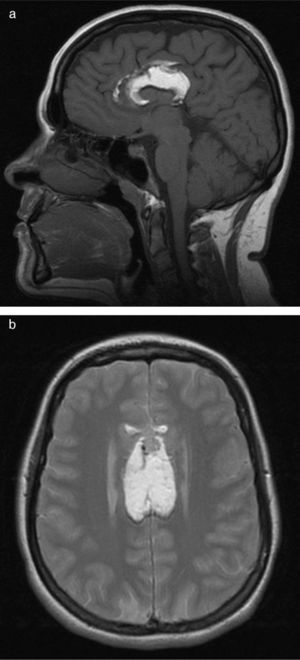

The patient visited the emergency department with symptoms of disorientation and buccofacial movements suggesting complex partial epileptic seizure. Neurological examination was normal. The cranial CT scan carried out in the emergency department (Fig. 1) showed absence of the corpus callosum and a hypodense homogeneous lesion in its location. We observed curvilinear calcifications on both sides of the lesion. Findings suggested agenesis of the corpus callosum with interhemispheric lipoma. Treatment with valproic acid was prescribed. The electroencephalogram showed epileptiform activity in the left temporo-parietal region. Brain MRI (Fig. 2) showed that the entire corpus callosum from the genu to the splenium was occupied by tissue that was hyperintense on all sequences, with the exception of the fat suppression sequence. The sagittal sequence showed bands of tissue that may correspond to remnants of the normal corpus callosum located between the lipomatous areas. We also observed slight dilation of the posterior horns of both lateral ventricles.

The appearance of the corpus callosum lipoma on the cranial CT scan is quite typical, with the low attenuation seen only in adipose tissue. In addition, it is surrounded by bilateral, rounded mural calcifications. After administration of contrast, the lesion showed no changes. In the brain MRI the lesion presents characteristics of fatty tissue, with a hyperintense signal in both T1- and T2-weighted studies.3 During complete agenesis of the corpus callosum, the lateral ventricles are far apart and never converge. They often have small frontal horns and disproportionally thick occipital horns (colpocephaly).